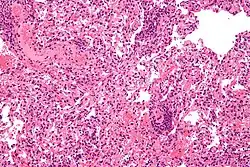

| Micrograph showing lung transplant rejection. Lung biopsy. H&E stain. | |

Acute cellular rejection occurs following direct allorecognition of mismatched donor MHC by cytotoxic T-cells that begin to secrete cytokines to recruit more lymphocytes as well as cause apoptosis or cell death directly.[4][6] The greater the difference in MHC between donor and recipient, the more cytotoxic T-cells are recruited to damage the graft,[6] which may be seen via biopsy in solid organ transplants, with increased lymphocyte infiltration indicative of more severe acute cellular rejection.[15] Acute humoral rejection is a process usually initiated by indirect allorecognition arising from recipient helper T-cells.[6] These helper T-cells have a crucial role in the development of B-cells that can create donor-specific antibodies.[4] The antibodies deposit themselves within the donor graft and lead to activation of the complement cascade alongside antibody-mediated cytotoxicity with neutrophils, a type of white blood cell separate from lymphocytes, predominantly infiltrating into tissues.[6]